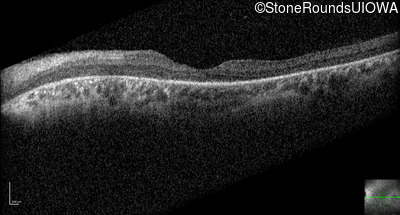

Optical Coherence Tomography - Right - 20/100

Exemplar / OCT Stack

OCT Stack